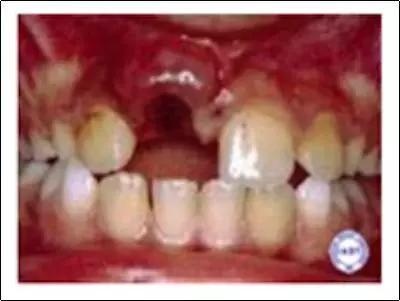

牙齿不是工具,虽然它足够硬,但请你把它当“瓷器”一样爱护吧。不然,等着你的结果可能是这样: